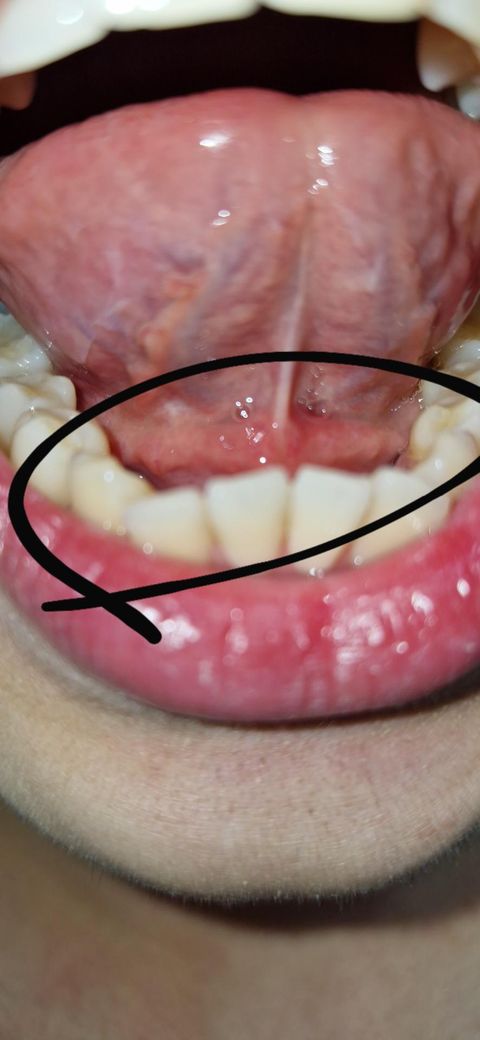

혀 밑에 이상한 살점? 같은게 있어요. 이쪽이 아프거나 하지는 않는데 뭔가 부어있는 것 같아요. 정말 부은건가요? 원인은 뭐가있나요?

그리고 앞니 잇몸과 혀 아래 사이 하얀색깔 점박이 같은게 있는데 이것도 문제있는건가요?

무통(통증이 없는) 위의 병변 같은경우

혀밑샘(침샘)의 낭종이 가장 의심됩니다.

혀밑샘 낭종의 증상으로는

통증이 없으며, 투명한 혹처럼 만져지고 식사 후 조금더 커지는 소견이 있습니다.